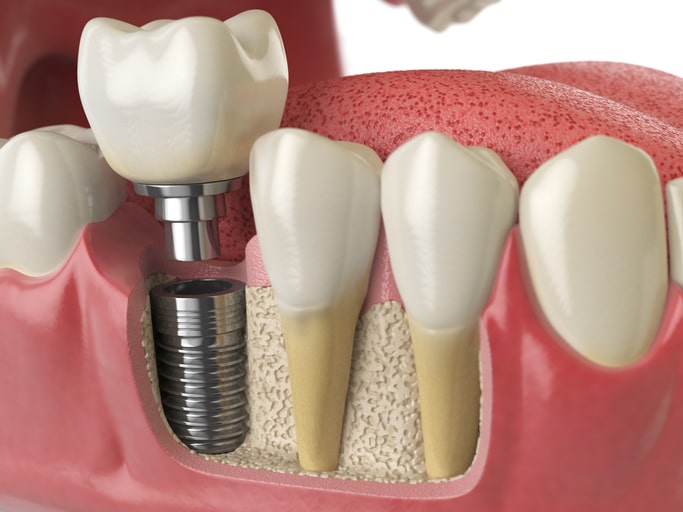

Das Prinzip : Das Implantat ersetzt die Wurzel eines Zahnes,

der Zahnersatz wird über einen Pfosten im Implantat verankert